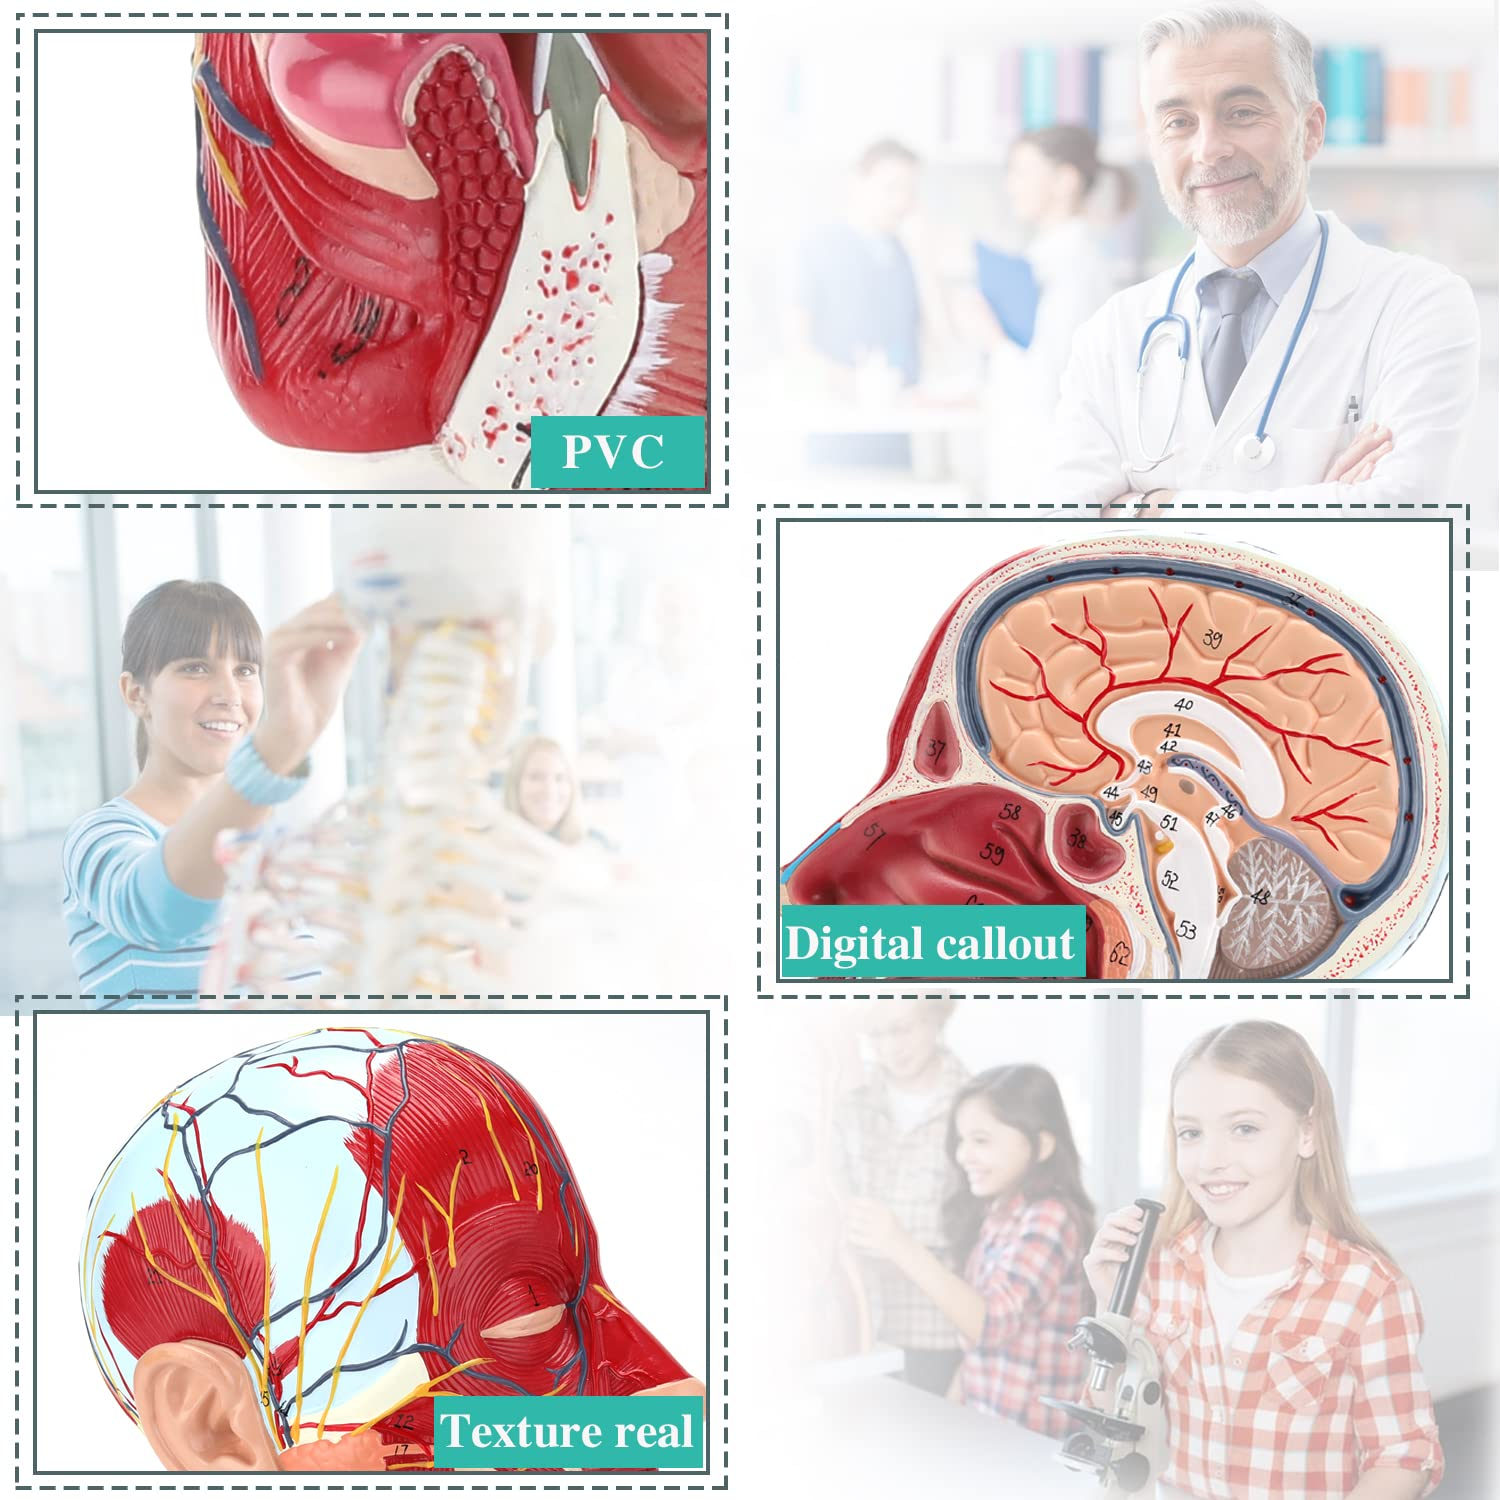

| Material | PVC |

【Model de anatomie a creierului de înaltă calitate, realizat din material din PVC ecologic non-toxic, ușor de curățat. Modelele de anatomie sunt pictate manual și asamblate cu cea mai mare atenție la detalii.

【Model de mușchi neurovascular superficial】 extrem de detaliat, numere marcate, detașabile, adânciți înțelegerea mușchilor superficiali, vaselor, nervilor și structurilor interne ale capului și gâtului. Red-Artery, vene albastru, galben-port.